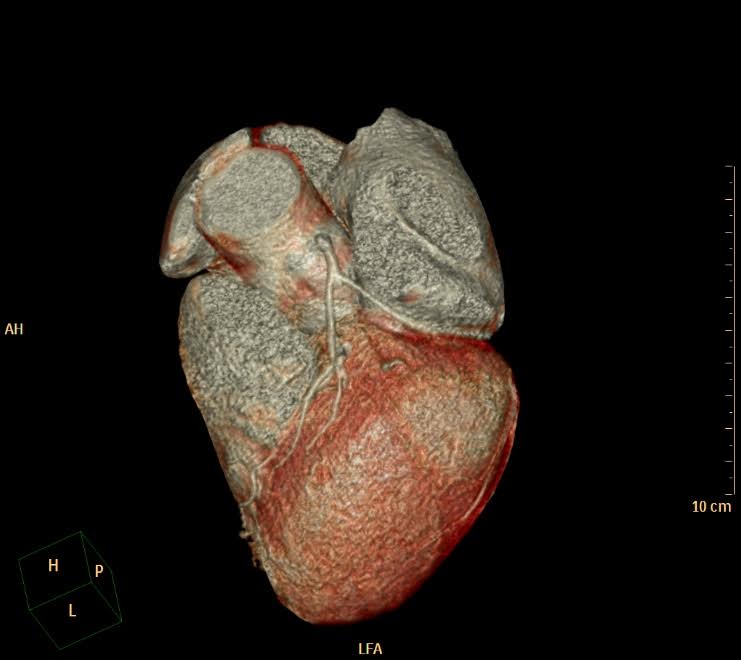

TC MULTISTRATO A BASSA DOSE (64 STRATI)

• Angio Tc Encefalo